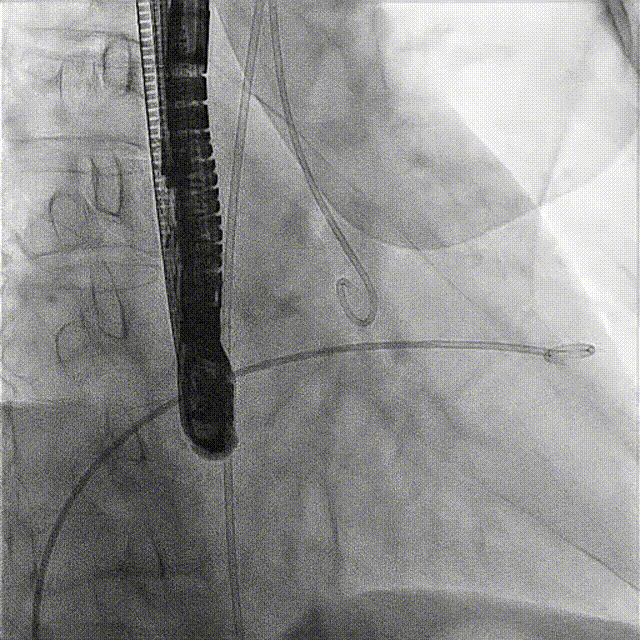

術(shù)前DSA

術(shù)前經(jīng)過全面系統(tǒng)的評(píng)估后,考慮患者存在高齡、心功能減低、三尖瓣瓣環(huán)重度擴(kuò)張(三尖瓣極重度反流)等高危因素,因此廈心結(jié)構(gòu)心團(tuán)隊(duì)聯(lián)合超聲心動(dòng)、麻醉及護(hù)理團(tuán)隊(duì),制定了詳盡的圍術(shù)期治療方案及術(shù)中治療難點(diǎn)預(yù)案。術(shù)中,由王焱院長(zhǎng)主刀,在蘇茂龍主任超聲心動(dòng)團(tuán)隊(duì)的輔助,上海市第一人民醫(yī)院陸方林主任的協(xié)助下,僅用時(shí)30分鐘,即順利完成了三尖瓣原位置換的手術(shù)。術(shù)中患者血流動(dòng)力學(xué)穩(wěn)定,術(shù)后即刻顯示LuX-Valve Plus瓣膜位置良好,固定穩(wěn)定,瓣膜功能正常,無(wú)瓣周漏。